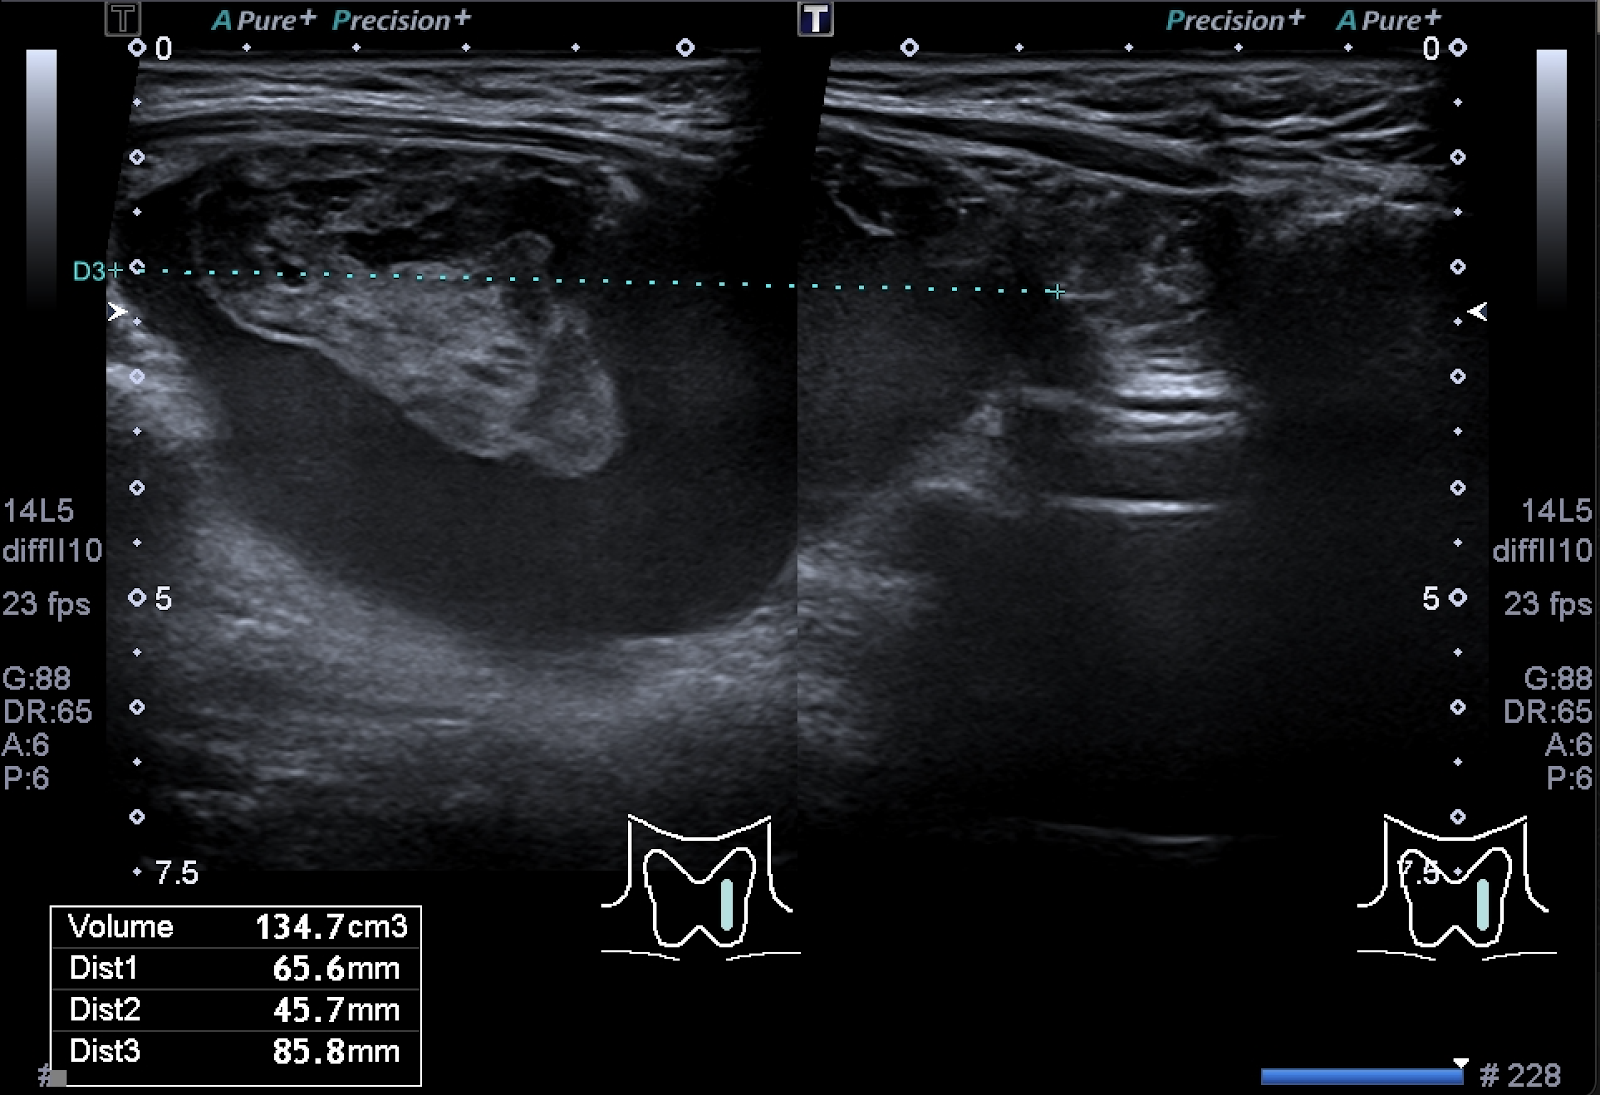

Exame pré alcoolização: volume de 135mL